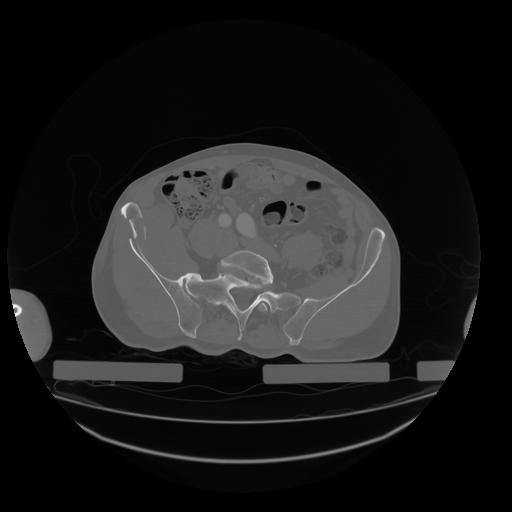

28 CUERPO,CE,Vol,2.0,CUERPO,,